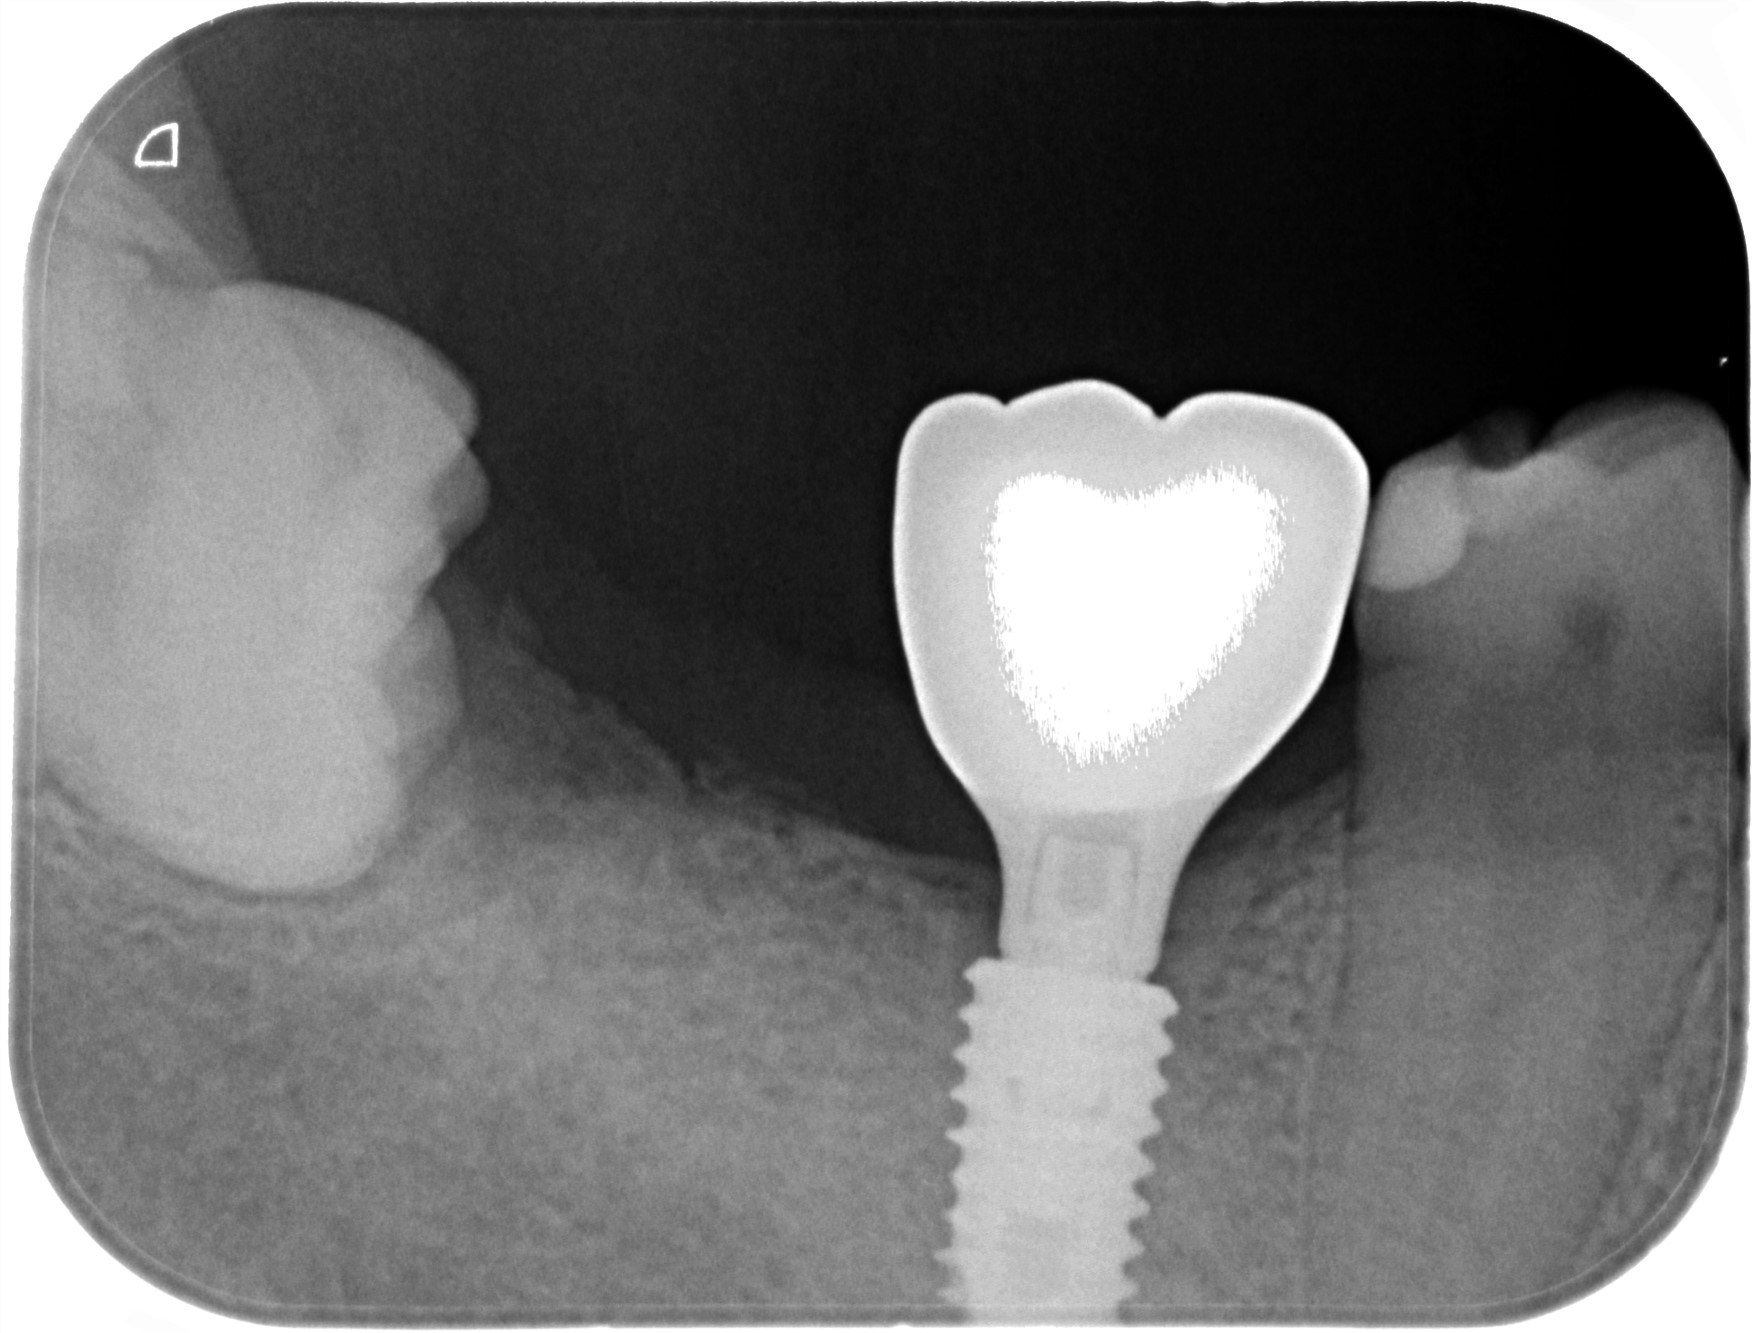

治療後

レントゲン写真

- 治療名称

- 右下6番欠損によるインプラント治療

- 患者の症状

- 20年前に抜歯してからそのままなのでどうにかしたい。

- 治療内容

- まず、CT撮影による精密な骨の分析・治療計画を立てガイドを使いインプラント埋入しインプラントが骨と結合するのを待つ間に仮の歯を入れます。その後本歯を作成して装着しました。

- 治療期間・回数

- インプラント埋入からジルコニアセットまで二か月半

- 費用

※自由診療となります - ■総額¥330,000(税込み) ■内訳:埋入(ガイド込み)¥200,000、仮歯¥20,000、被せ物(ジルコニア)¥80,000

- リスク・副作用

- ・術後の腫れ・痛み・出血 ・感染(インプラント周囲炎) ・インプラントの脱落 ・神経損傷によるしびれ ・破損・ゆるみ